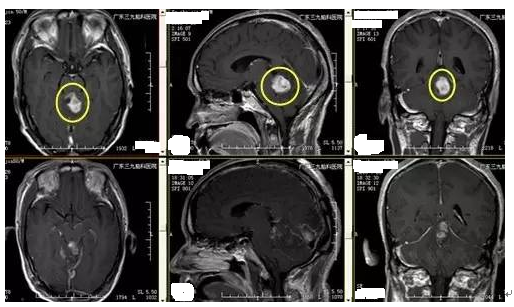

↑手术前后MR对比

间变型星形细胞瘤治疗为手术、放疗、化疗等的综合治疗,直视下全切除极为困难。有研究表明,根治性切除和部分切除两组的5年肿瘤无进展生存率分别为(44±11)%和(22±6)%,因此手术应争取全切除。本例患者病变位置较深,与脑干关系密切,术后MR示病变基本全切除,术后恢复良好,眩晕症状缓解,未有明确并发症。